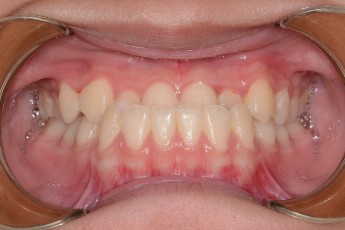

BEFORE & AFTER

- 덧니교정